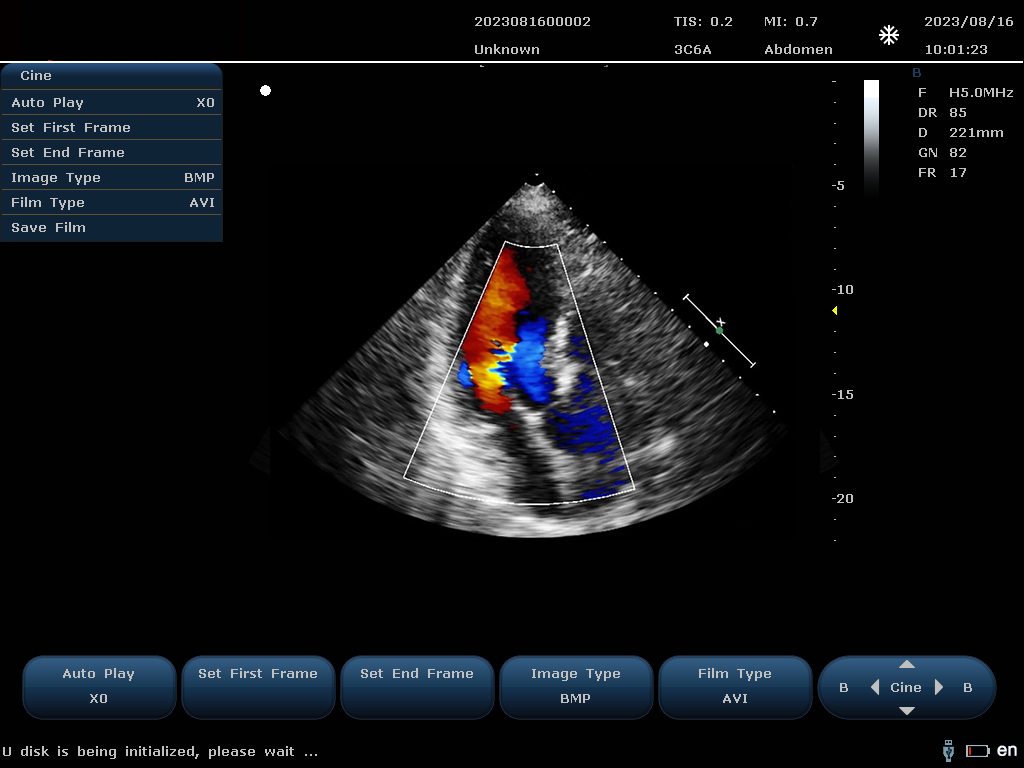

設(shè)備通過檢測這些頻移信號,并利用復(fù)雜的信號處理技術(shù),包括傅立葉變換等,分析血流的方向、速度和分布。彩色編碼后,血流信息被疊加在傳統(tǒng)的黑白超聲二維圖像上,形成彩色多普勒圖像,直觀顯示血流動態(tài)。

最終,這些信息轉(zhuǎn)化為圖像顯示在屏幕上,醫(yī)生可以根據(jù)圖像中血流的顏色(通常紅色代表血流朝向探頭,藍(lán)色代表遠(yuǎn)離探頭)和亮度來判斷血流的性質(zhì)和異常情況,如血流速度增快可能指示狹窄,無血流區(qū)域可能意味著阻塞等。